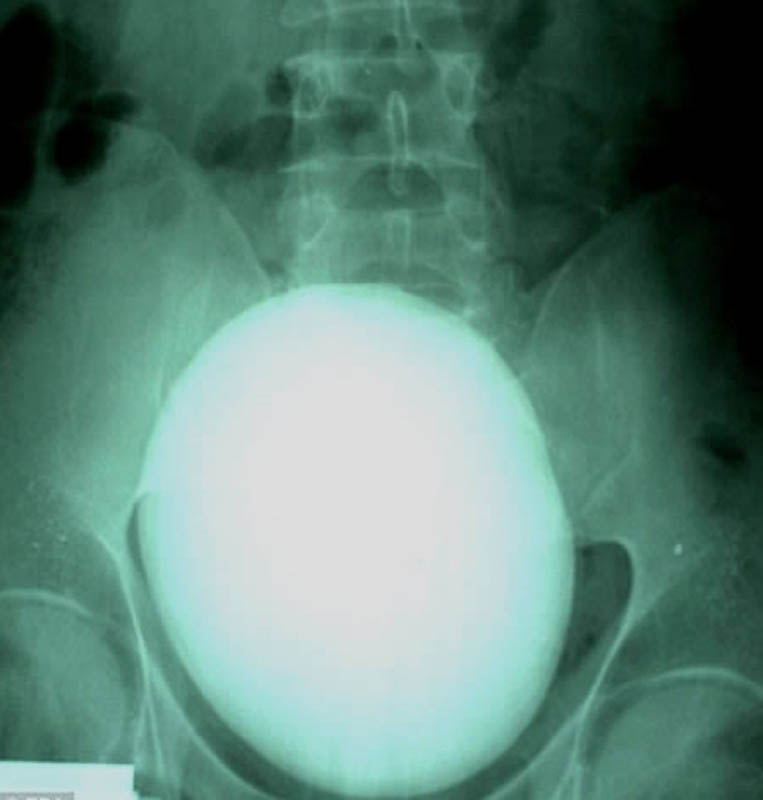

Бутылка из-под «Пепси» в анусе 60-летнего мужчины